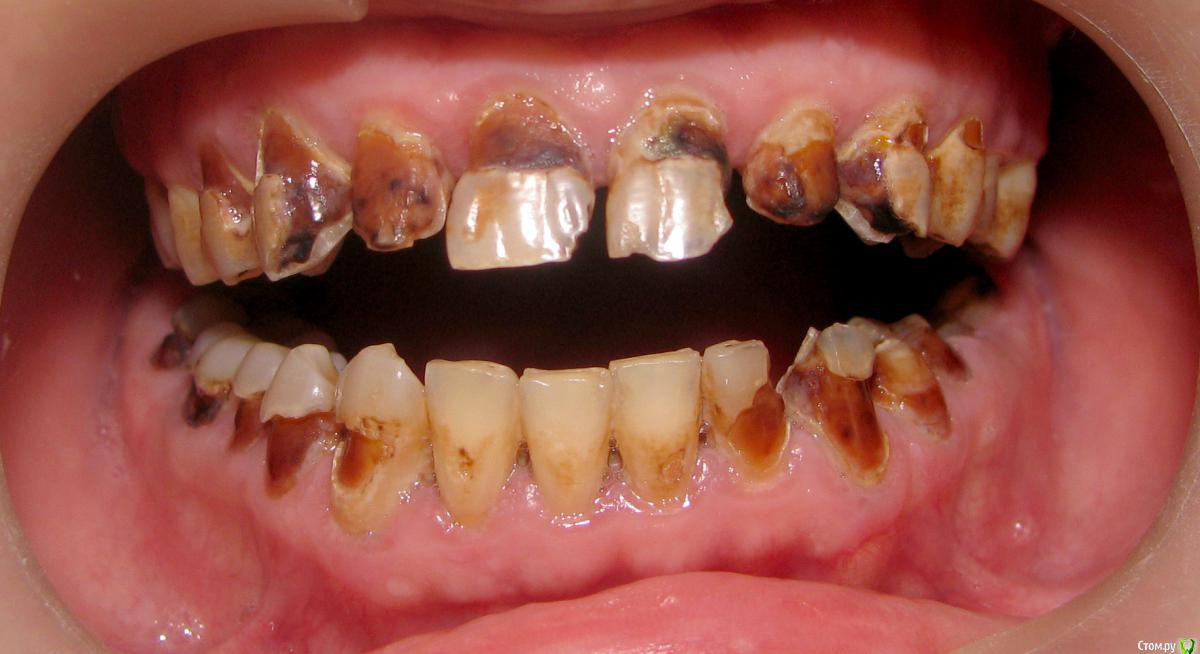

Alex52 Опубликовано 27 июля, 2015 Поделиться Опубликовано 27 июля, 2015 Первичка, наркоту отрицает, со слов практически здоровЛет 20 за компом - с этим и связывает свое состояние. Так и хочется поставить такой диагноз - компьютерный некроз, но не понимаю патогенез, он же не с куском плутония целовался.Пигментированные ткани почти все мягкие (не сильно), на температуру реагируют.Коллега предлагает сделать курс ремотерапии, чтобы пигментация была с крепитацией, а потом лечить по диагнозу, может что и живое останется и вкладок поменьше - но что-то слабо верится в такой курс. Ссылка на комментарий

lehadoc Опубликовано 28 июля, 2015 Поделиться Опубликовано 28 июля, 2015 Прямо с моего пациента всё списано. Нарик 100%. Мне также про комп и всё прочее мозги втирали пока я пазлы не сложил.Очень сложно с такими работать.Пик был ,когда пульпит лечил 25 зуба без анестезии. Ссылка на комментарий

faity Опубликовано 28 июля, 2015 Поделиться Опубликовано 28 июля, 2015 я одно время работал в клинике которая сотрудничала с металлургическим заводом, там таких много было из-за отравления непонятно чем. Ссылка на комментарий

brg Опубликовано 28 июля, 2015 Поделиться Опубликовано 28 июля, 2015 курит?Курит!!!Смеси-спайсы, был у меня похожил как на фотоОн сам сразу сказал -курил, завязал.Хочу новые зубы 1 Ссылка на комментарий

gum Опубликовано 30 июля, 2015 Поделиться Опубликовано 30 июля, 2015 Так в итоге какой прогноз, кто таких протезировал. У меня сейчас девушка с такой картиной, у эндокринолога лечится. С ее слов. Жду заключения врача. Так у нее дентин весь мягкий эмаль крошится. Кроме как все удалять есть еще варианты? Так как коронки потом падать начнут. Ссылка на комментарий